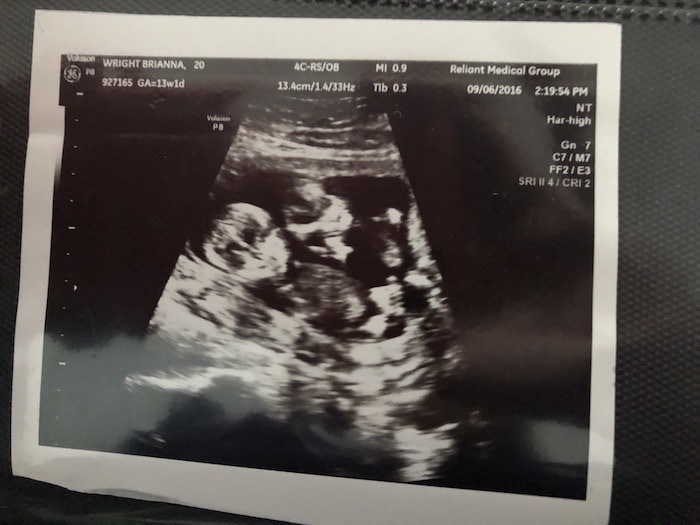

- Ultrasound Photos at 13 Weeks Pregnant With Twin

Ultrasound Photos at 13 Weeks Pregnant With Twin